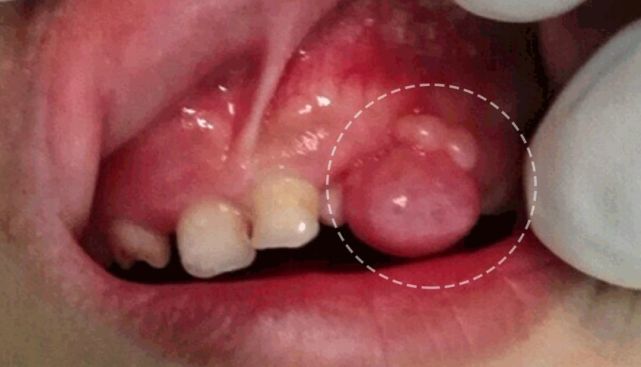

炎症性牙龈增生累及牙间区域和龈缘

牙龈组织变得肥大并充血

这叫做牙龈过度生长,如果孩子平时刷牙不认真,没把牙龈附近的细菌给刷干净,细菌大规模繁殖后便会引起炎症,让牙龈肥大、充血,仿佛长了个包,有时需要进行牙龈切除术。

此外,孩子长期服用一些药物(如苯妥英钠、硝苯地平和环孢素A等),或患有全身浸润性疾病(如白血病)、遗传性牙龈纤维瘤病等,也会引起牙龈过度生长。 |